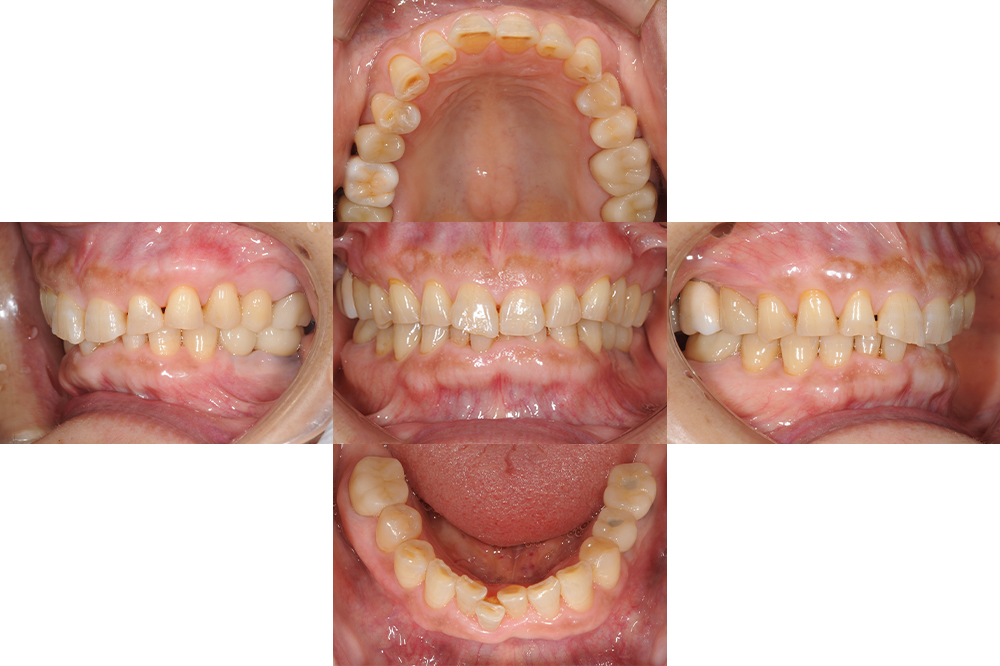

治療経過 全体的に歯が磨耗し、下顎奥歯には義歯が装着されていたが義歯は破損し使えていない状態であった

今回奥歯でしっかり咬めるようにしたいということで欠損部にはインプラント治療を、少しでも清掃性を良くしたいという目的でセラミック修復を希望された。

元々全体的に歯と歯の間がすいていて食渣が挟まりやすかったが、インプラントを入れることで奥歯にしっかりしたサポートが回復され、歯の隙間が自然と詰まり、物詰まりも軽減することができた。

Before